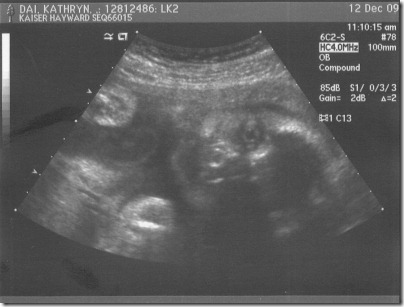

Day 308: baby face

At our ultrasound last Saturday, we got a gander at the baby’s face.

The detail and crispness of the image was amazing and a bit scary.

Here he is, staring at you:

Check out that massive eye!  It’s like he’s staring into your soul.